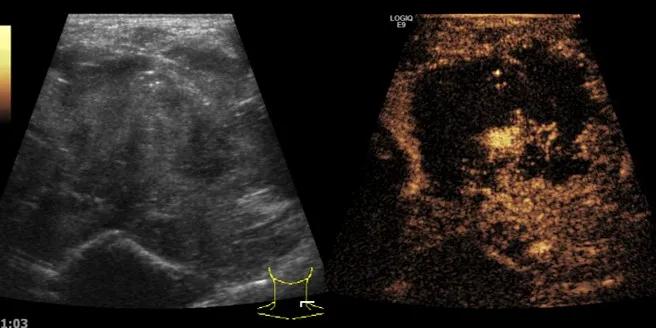

随后,徐栋教授进一步分享了五个临床实战病例,带来了更直观的热消融治疗经验。第一个病例是62岁肺癌患者,术后1年余发现双侧锁骨上淋巴结复发,侵犯神经,存在静脉回流、淋巴回流障碍,肿胀、疼痛非常明显。影像显示患者淋巴结边界不清、形态不规则,存在浸润,血流强化增强。由于患者在系统治疗后进展,且主要目的缓解症状、减瘤。局麻下行热消融术,从后向前逐层消融,热消融之后超声造影即刻评估显示完全充盈缺损,完全覆盖病灶。

(病例1图例)